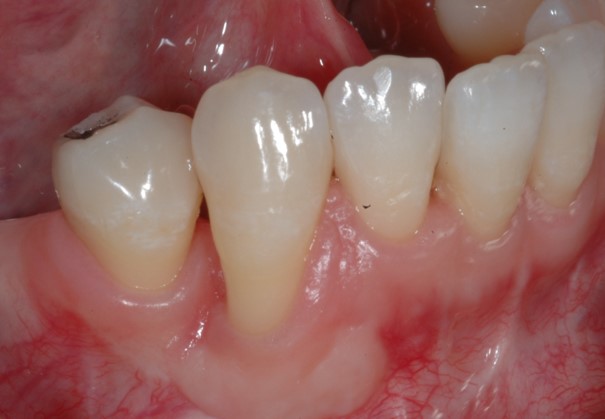

Fig 15. A tunneling procedure with a small connective tissue graft was performed to establish extra soft tissue with a thickened biotype.

Figure 15

Fig 16. Close-up view of the patient’s gingival architecture following tissue graft healing.

Figure 16

However, by giving consideration to the most appropriate and minimally invasive sequence of care, this led to performing predictable procedures beginning with a tunneling procedure with a small connective tissue graft (Figure 15). Once the connective tissue graft healed (Figure 16), extra soft tissue with a thickened biotype was available. This would enable minimally invasive extraction using piezosurgery—without damaging the soft tissues (Figure 17)—followed by immediate implant placement according to 3D implant treatment planning (Figure 18 through Figure 20).